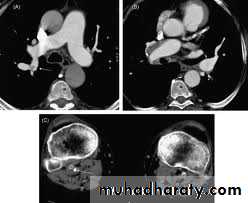

CT pulmonary angiography (CTPA)

It visualizes the distribution and extent of emboli in positive cases.

It may also prove alternative diagnosisSimultaneous visualization of femoral and popliteal veins for DVT improves sensitivity.

Can be performed safely in pregnant women (with foetal shielding).